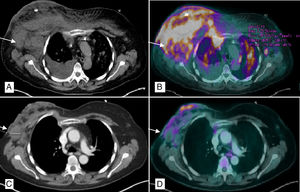

Biopsy of the breast lesions showed evidence of epidermal spongiosis and small cells with irregular nuclei, limited cytoplasm and predominant CD4 positivity compatible with CD30+ T-cell non-Hodgkin lymphoma (HTLV−). PET/CT (Fig. 1A and B) demonstrated evidence of subcutaneous involvement in both breasts, multiple supra- and subdiaphragmatic, splenic and pulmonary lymphadenopathies related to the progressing lymphoproliferative syndrome. We decided to initiate palliative treatment (methylprednisolone, cyclophosphamide, etoposide and procarbazine) with an excellent response, so we decided to discharge the patient until hematological recovery. Two months later, treatment was suspended due to febrile neutropenia and the patient came to the emergency department with superinfection of the breast tissue and complete necrosis of the breast (Fig. 2A).

PET/CT chest scan: (A) Multiple bilateral axillary lymphadenopathies, the largest on the right measuring 4cm (arrow), with subcutaneous involvement of both breasts, predominantly right, and ipsilateral pleural effusion; (B) Pathological uptake of 18F-FDG (fludeoxyglucose) in the right breast, left breast, right lower sulcus and bilateral pulmonary parenchyma (millimeter nodules) related with the lymphomatous infiltration; (C) Decrease in the overall size of the right breast with air bubbles in its interior related with necrosis and reduction of axillary lymphadenopathies, the largest right measuring 2.9cm; (D) Morpho-metabolic improvement of the lymph node, pulmonary and subcutaneous cellular tissue involvement, suggestive of a good response to treatment.

The patient was admitted and, after hematological recovery, the regimen was reinitiated, with radiological improvement (Fig. 1C and D) and delimitation of the necrosis, at which time it was decided to perform hygienic mastectomy to improve local control of symptoms. During surgery, almost complete detachment of the gland was observed, with a stony consistency due to the necrosis and purulent material inside (Fig. 2B). A simple mastectomy was conducted with partial pectoralis major and minor excision in areas that had been more affected by necrosis, while also eliminating several lesions in the sternal region. Immediate reconstruction was ruled out due to the infectious process and the difficult systemic control of the disease.